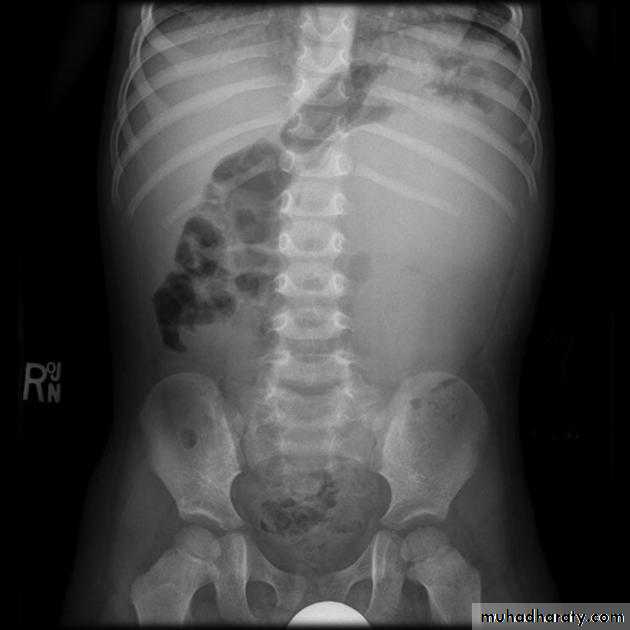

Wilms tumor

Abdominal x-ray typically reveals a large soft tissue opacity displacing bowel shadowNormal US of the renal system